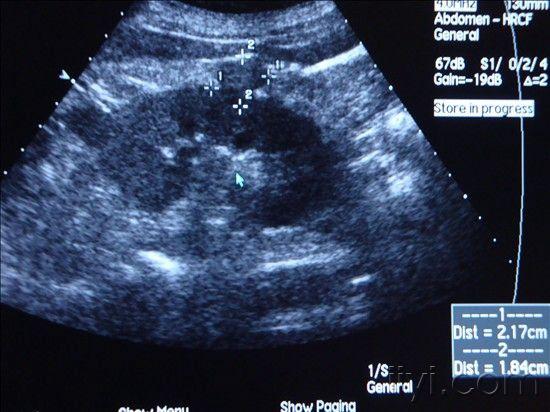

肾肿瘤彩超

肾肿瘤彩超,肾肿瘤ct

肾肿瘤超声鉴别诊断

肾结核?肾肿瘤?

体检时超声要尽量防止漏诊肾癌